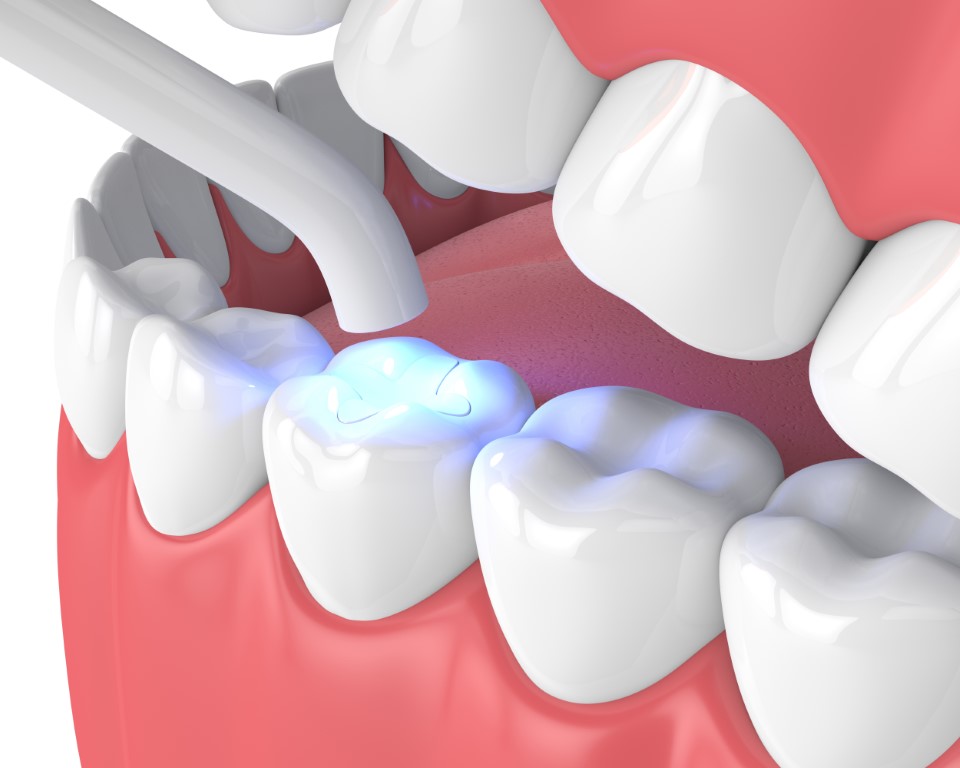

After choosing the type of filling, the dentist will proceed to treatment. This may entail removing the damaged or decayed part of the tooth. The affected tooth will then be cleaned and prepped before the filling is applied directly to the tooth.

If you choose a white filling, this helps the dentist to retain more of your natural tooth as, unlike a metal filling, the composite resin is bonded directly to the natural too just like a normal filling, a white filling helps to restore a tooth that has been damaged by decay, strengthening it and protecting it from deteriorating further. The added benefit of a white filling, however, is that it blends into the mouth, so your treatment is invisible yet effective.